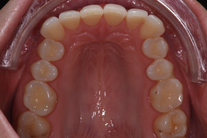

Tandreglering 5

32-årig kvinna som tycker att hon bara visar sina framtänder. En utjämning och vidgning av tandbågen med 8 månaders genomskinliga Invisalignskenor, gav henne ett fint leende.